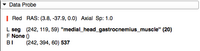

The Data Store allows a user to easily upload and download MRB files.